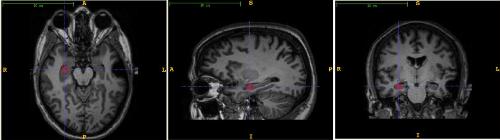

En un estudio realizado por Rasmussen et al. (2015) se compararon personas sanas y personas con el síndrome de Cushing. Se observó que existía una alteración en la sustancia gris del cerebro. Aspecto que revelaría la atrofia cerebral en los pacientes diagnosticados, como el déficit en la velocidad de procesamiento y la cognición. Resultados que exponen el grave deterioro en quienes presentan dicha condición.